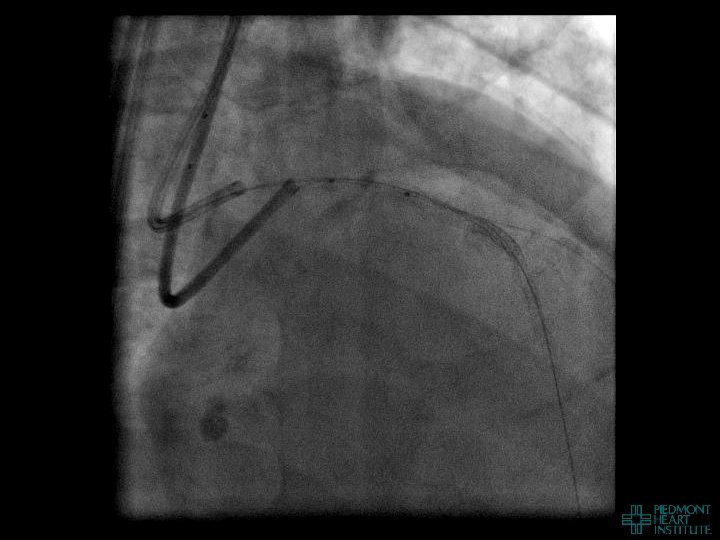

Coronary Perforation Methods of Patient Management • Dual Catheter (‘Ping Pong’) Technique • Prolonged

Coronary Perforation Methods of Patient Management • Dual Catheter (‘Ping Pong’) Technique • Prolonged balloon inflation and covered stents • Reversal of anticoagulation — Know contradictions to protamine sulfate for UFH; Avoid bivalirudin, LMWH — Reserve GP 2 b 3 a inhibition until successful crossing and wire change-out Embolization • — Coil, gelfoam, methacrylate, autologous blood/fat • Microcatheter Occlusion • Confirmation of successful management — Contralateral injection — Right heart catheterization — Echocardiogram — Contrast echocardiography